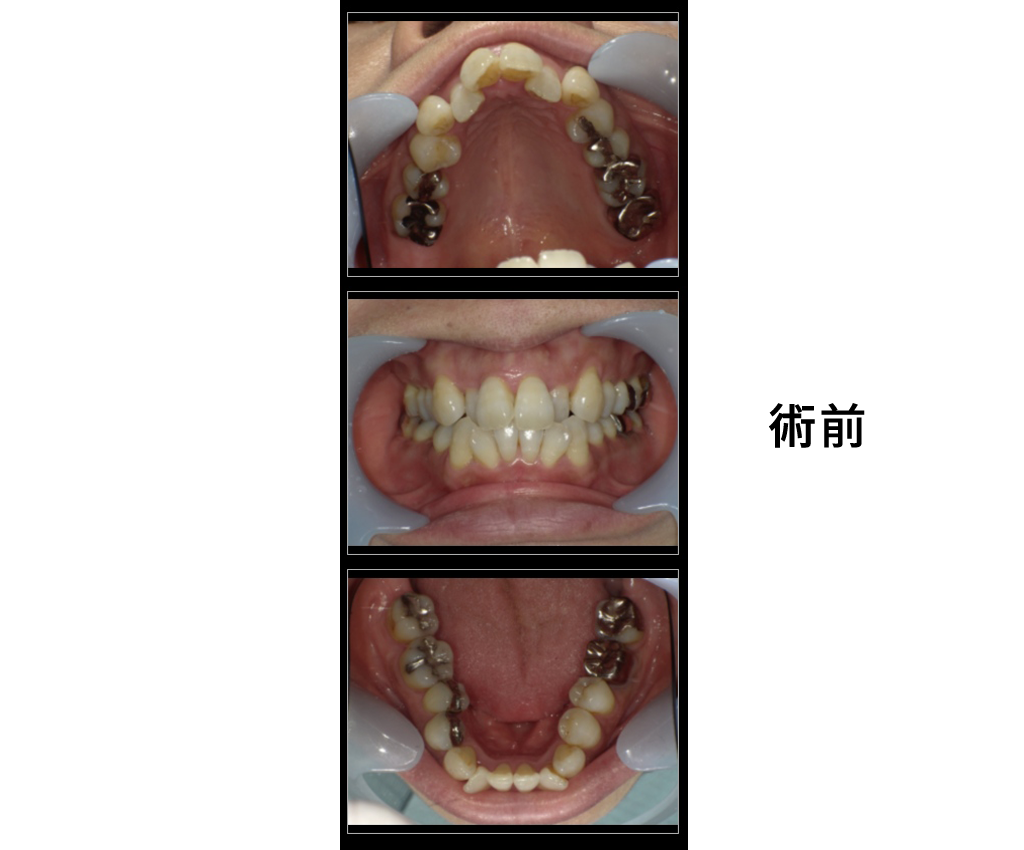

女性・25歳

治療内容:前歯の被蓋をなおしたい

→インビザラインGOにて矯正治療

金額:診断22000円、矯正440000円

来院理由:前歯の歯並びを治したい

施術の副作用(リスク):

痛みや違和感を感じることがあります。歯が一時的に動揺することがあります。

咬みにくさをかんじることがあります。